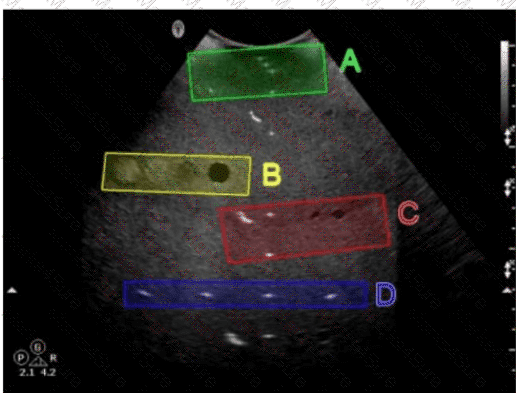

Questions 33

Which target group is used to evaluate transverse distance measurement accuracy in this tissue-mimicking phantom image?

SPI Question 33

Options:

A.

Option A

B.

Option B

C.

Option C

D.

Option D